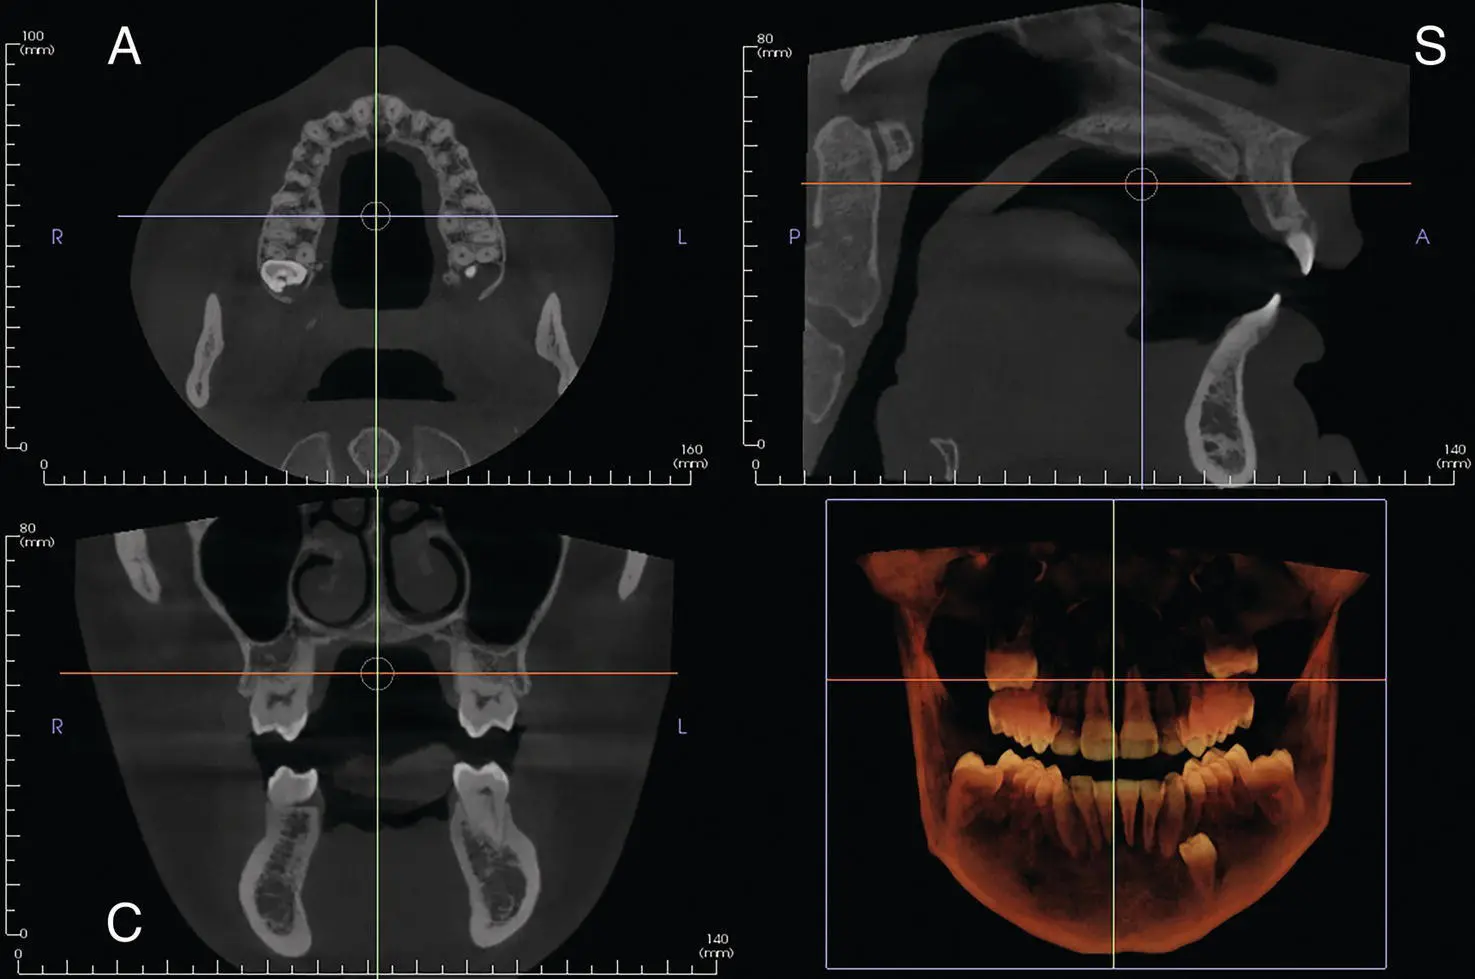

Figure 1.6. Axial (A), coronal (C), sagittal (S), and reconstructed 3D views from large FOV.